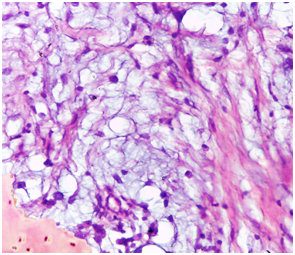

Histologically, the overlying epithelium displayed signs of pseudoepitheliomatous hyperplasia. The connective tissue revealed an impressive myxomatous background, in which lobules of myxoid areas were conspicuous (Figure 2). Evident in the histological field was the occasional peripheral bone formation, which embraced the myxomatous stroma (Figure 3). The focally rich fibrocellualrity of the lesion should neither mitotic figures nor cellular atypia. Neither granuloma formation nor malignant features could be appreciated (Figure 4). The diagnosis was, accordingly, an ossifying fibromyxoid tumor. Regarding confirming the diagnosis of OFMT, no immunohistochemical markers were indicated because no specific markers are adjunctively recruited in the medical literature. A follow-up interval was determined: every 6 months. The patient was educated about the necessity of compliance.

Figure 3 Photomicrograph characterizing occasional peripheral bone formation, which embraced the myxomatous stroma. (H&E stained, Original magnification: 40x).